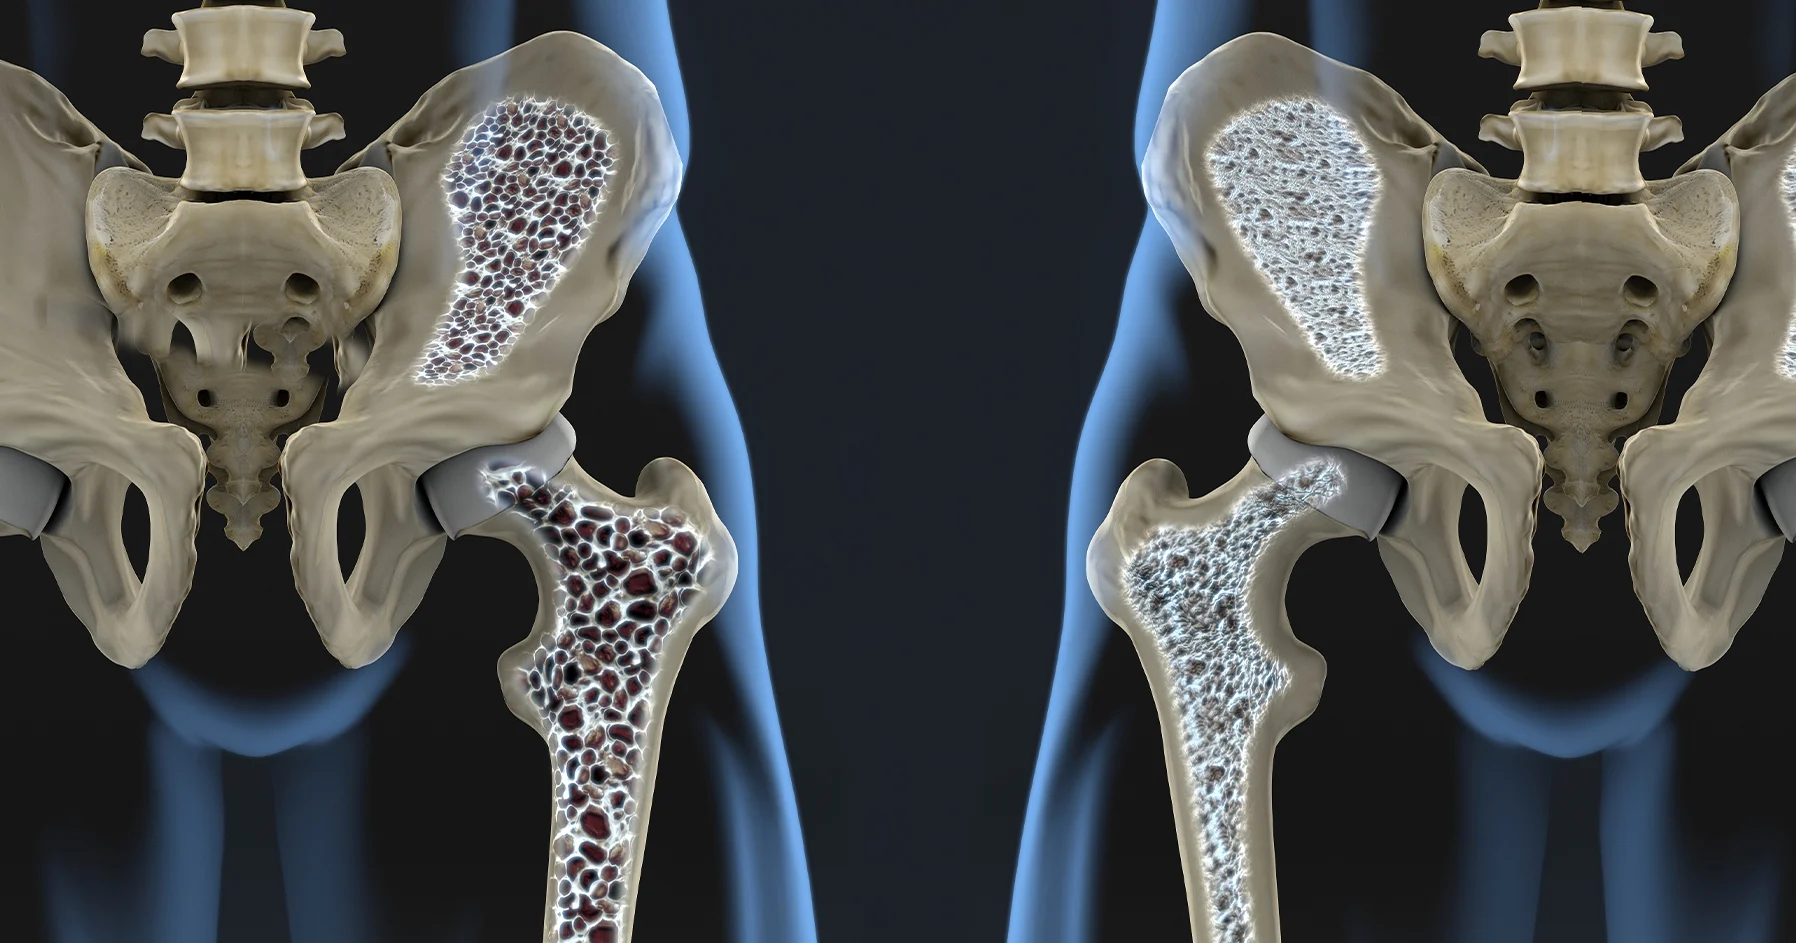

Osteoporosis

Osteoporotic spine fractures are a prevalent health issue, particularly among the elderly, characterized by fractures in the vertebrae due to weakened bone strength from osteoporosis.